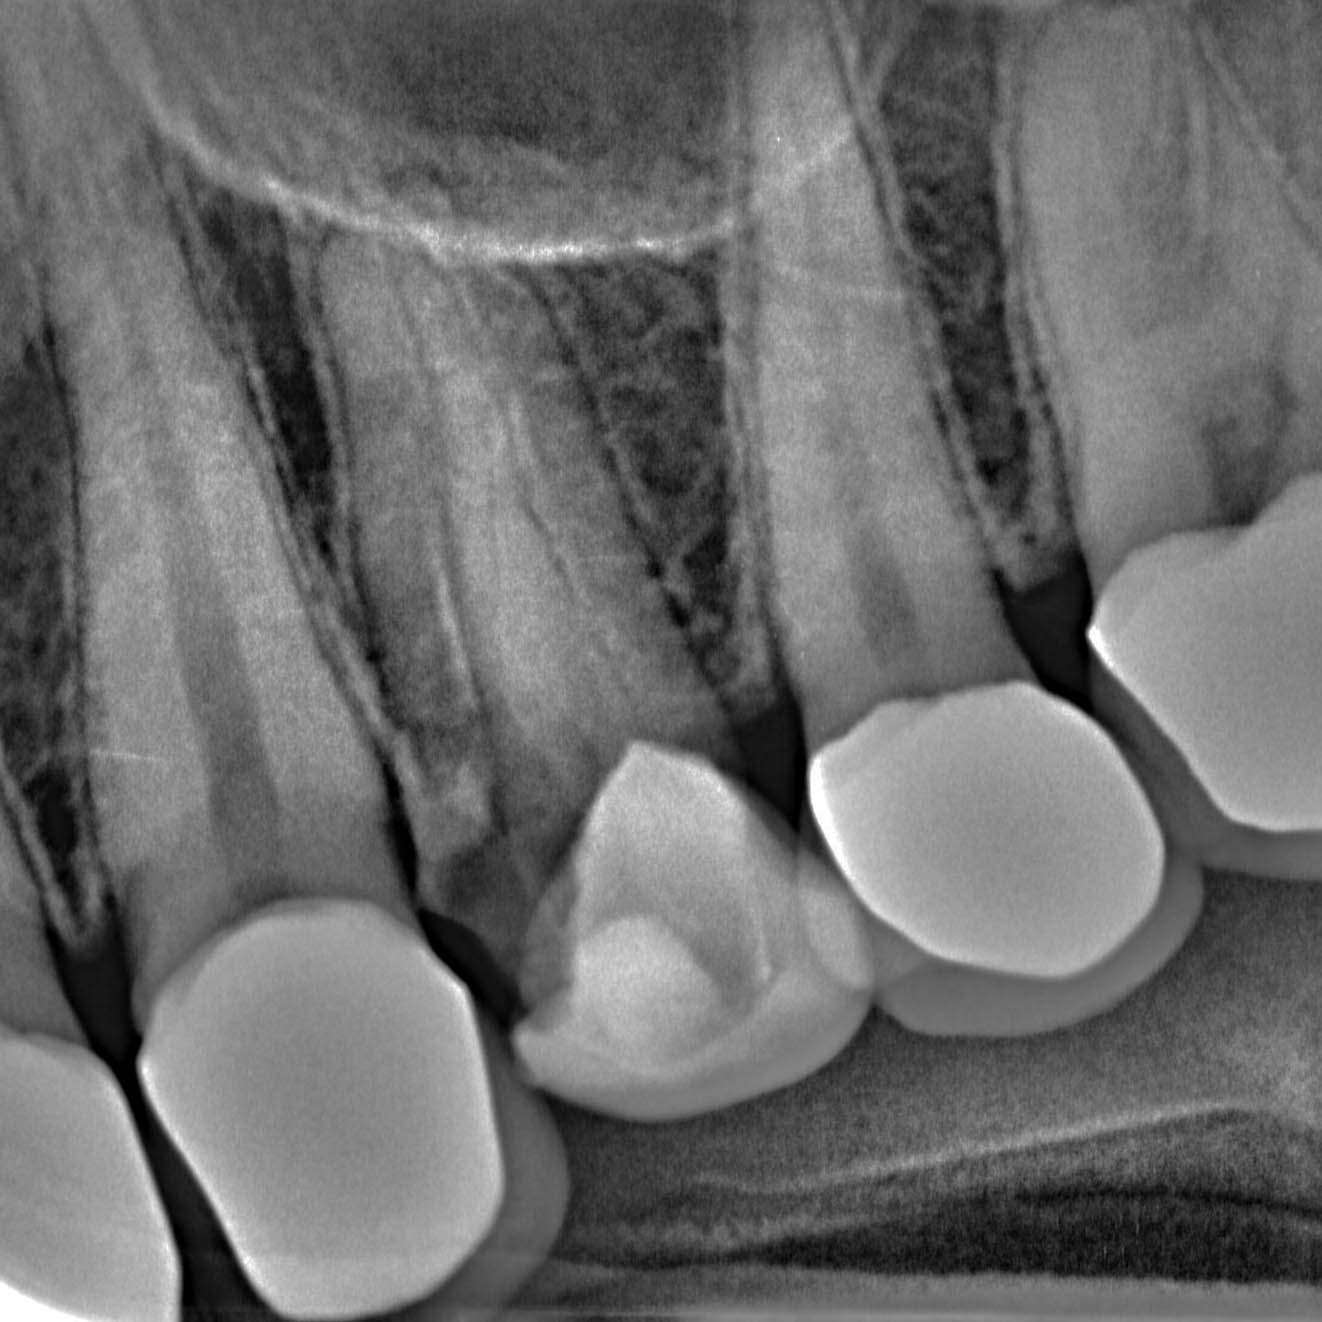

Die wichtigste Voraussetzung für ein Implantat ist die Planung. Während früher Implantate freihändig im Kieferknochen inseriert wurden, sollte heutzutage ein Implantat sowohl perfekt im Knochen, als auch an einer perfekt mit einer Krone versorgbaren Position eingesetzt werden. Hierfür benötigen wir zwingend 3D-Röntgenaufnahmen und 3D-Scans von Zähnen und Zahnfleisch, die digital übereinander gelegt erst eine sinnvolle Gesamtplanung ermöglichen.

Gemeinsam legen Zahnarzt und Zahntechniker dann die optimale Position für den neuen Zahnersatz fest und suchen hierzu passend die beste Möglichkeit für die Implantatposition. Mittels 3D-Druck fertigt der Zahntechniker eine exakte Bohrschablone für das Einsetzen des Zahnimplantats.